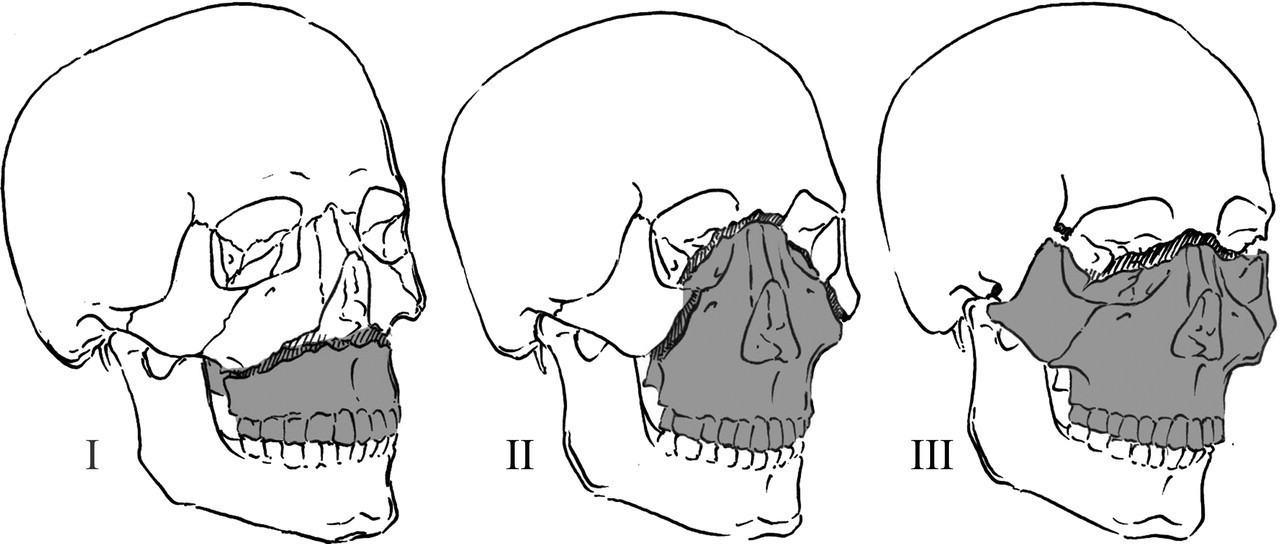

Il s’agit ici de reconnaître les principales caractéristiques cliniques de fractures de la face. Sans scanner à ce stade, on peut tout de même éliminer de principe les fractures de Le Fort qui correspondent à une séparation (à hauteur variable) entre le plateau palatin et la base du crâne. Ainsi, on peut cliniquement mobiliser le palais, ce qui n’est pas le cas ici. Les différentes fractures sont présentées dans la figure 1 : Figure 1 (source : Collège des enseignants de chirurgie maxillo-faciale) Le CNEMFO est une fracture typique à connaître (cf. correction question 4).

Il y a plusieurs fractures faciales chez ce patient. On retrouve en premier lieu une fracture du CNEMFO, ainsi que deux autres fractures : fracture du zygoma droit et fracture verticale du maxillaire droit.

Rappel sur le CNEMFO : une fracture du complexe naso-éthmoïdo-maxillo-fronto-orbitaire fait suite à un choc de haute vélocité centro-facial. Le point d’impact pourrait correspondre à une fracture des os propres du nez (OPN), mais l’importance du choc entraîne un écrasement complet de la pyramide nasale et une fracture des os environnants : l’os frontal vers le haut, l’orbite (paroi médiale et plancher), la branche montante du maxillaire, et l’os éthmoïdal en arrière. Lorsque la fracture est isolée, il n’y a pas d’atteinte du zygoma.